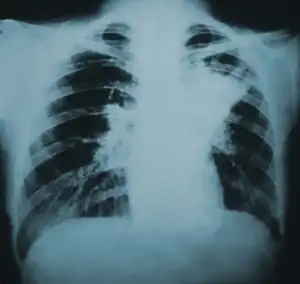

![]() | |

| Lung infiltration in blastomycosis. | |

Blastomycosis manifests as a primary lung infection in about 79% of cases.[8] The onset is relatively slow and symptoms are suggestive of bacterial pneumonia, often leading to initial treatment with antibacterials. Because the symptoms are variable and nonspecific, blastomycosis is often not even considered in differential diagnosis until antibacterial treatment has failed, unless there are known risk factors or skin lesions.[8] The disease may be misdiagnosed as a carcinoma, leading in some cases to surgical removal of the affected tissue.[19] Upper lung lobes are involved somewhat more frequently than lower lobes.[20] If untreated, many cases progress over a period of months to years to become disseminated blastomycosis.

Blastomycosis in the lungs may present a variety of symptoms, or no symptoms at all.[8] If symptoms are present they may range from mild pneumonia resembling a pneumococcal infection to acute respiratory distress syndrome (ARDS).[8] Common symptoms include fever, chills, headache, coughing, difficulty breathing, chest pain, and malaise.[8] Without treatment, cases may progress to chronic pneumonia or ARDS.[8]